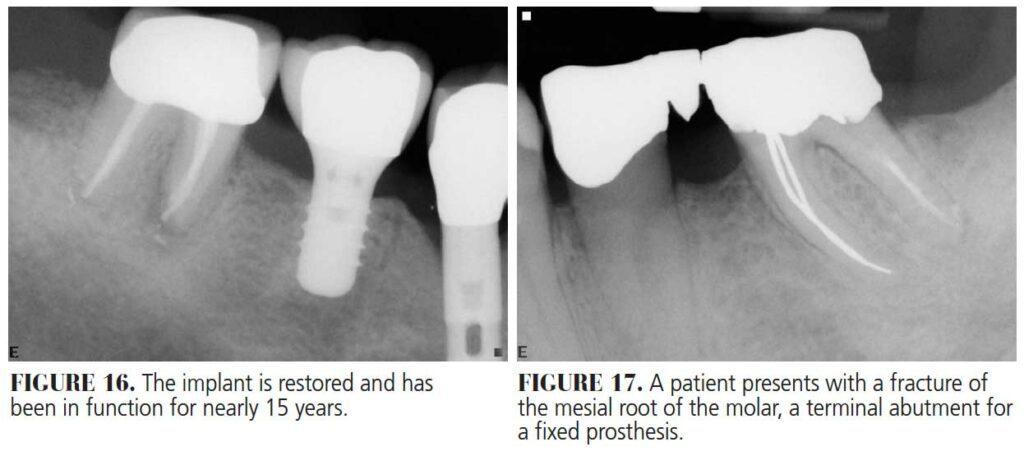

Following osseointegration of an ideally positioned implant in a molar socket, the dentist carries out the necessary restorative therapy. Ideally, an implant design that allows the crown to rest on the neck of the implant is preferable in these areas, as studies have demonstrated a reduction of stresses to both the peri-implant crestal bone and abutment interface when the crown rests on the implant body rather than the abutment (Figure 13 through Figure 18).